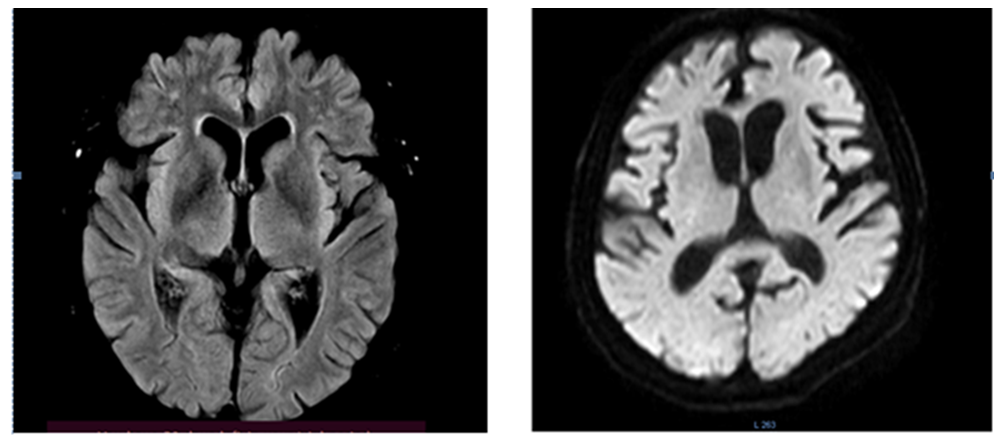

Thus, it can be concluded that signs of atrophy/hypotrophy of the brain, and even of the frontotemporal lobes, were observed not only in patients with frontotemporal dementia with clear signs of dementia, but also in patients with chronic cerebral ischemia. In this study, we see that the neuroimaging picture does not always correlate with clinical manifestations and the level of cognitive impairment. There is a high probability that patients with moderate and severe cognitive impairment will subsequently also move into the group with dementia, so earlier detection of such impairments and their timely correction are necessary. At the same time, signs of encephalopathy were more often observed in the group with mild cognitive impairment and severe cognitive impairment, which also speaks in favor of the vascular component of the pathology. Figure 7 shows MRI signs of atrophy of the frontal and temporal lobes of the brain.

Figure 7. Patient 67 years old. Atrophy of the frontotemporal regions of the brain